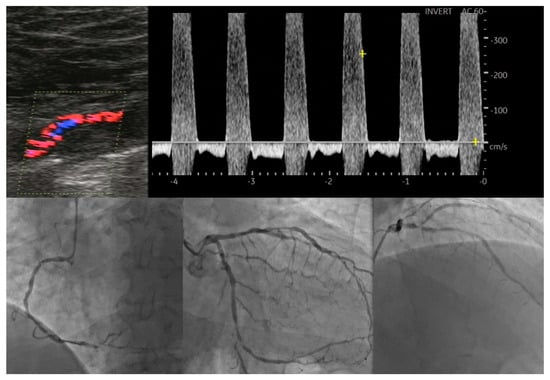

- Tătaru, D.A.; Olinic, M.; Homorodean, C.; Ober, M.C.; Spînu, M.; Lazăr, F.L.; Onea, L.; Olinic, D.M. Correlation between Ultrasound Peak Systolic Velocity and Angiography for Grading Internal Carotid Artery Stenosis. J. Clin. Med. 2024, 13, 517. [Google Scholar] [CrossRef] [PubMed]

- Artyszuk, Ł.; Błażejowska, E.; Danielecka, Z.; Jurek, J.; Olek, E.; Abramczyk, P. Peripheral atherosclerosis evaluation through ultrasound: A promising diagnostic tool for coronary artery disease. Echocardiography 2023, 40, 841–851. [Google Scholar] [CrossRef]